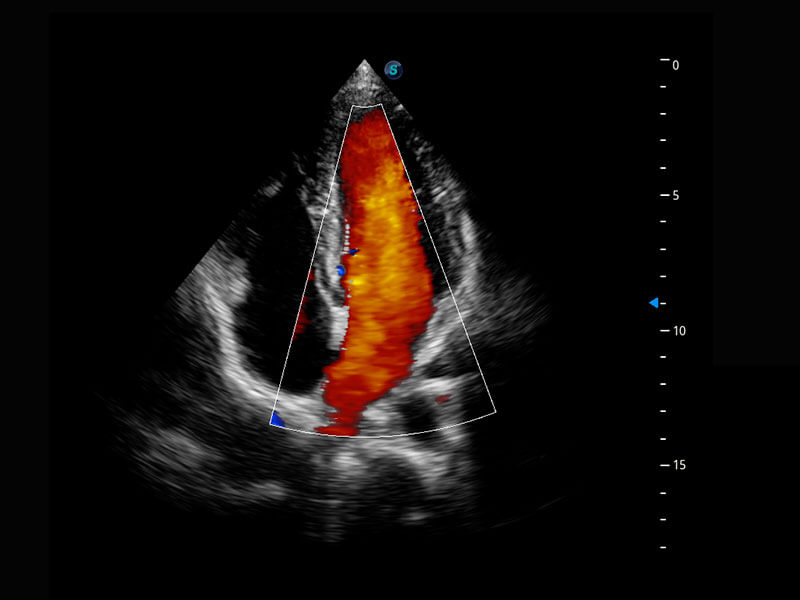

乳腺超声 / 新生儿

P60搭载宽频带线阵探头、宽景成像、弹性成像技术,为您提供乳腺应用方案。P60支持高频相控阵探头、线阵探头、腹部高频探头、腹部微凸探头等,丰富的探头群搭载敏感的彩色血流成像,适用于新生儿多种脏器检测要求,满足新生儿筛查需求。

• 新生儿肝血管癌

• 新生儿脊髓圆锥

• 新生儿心脏